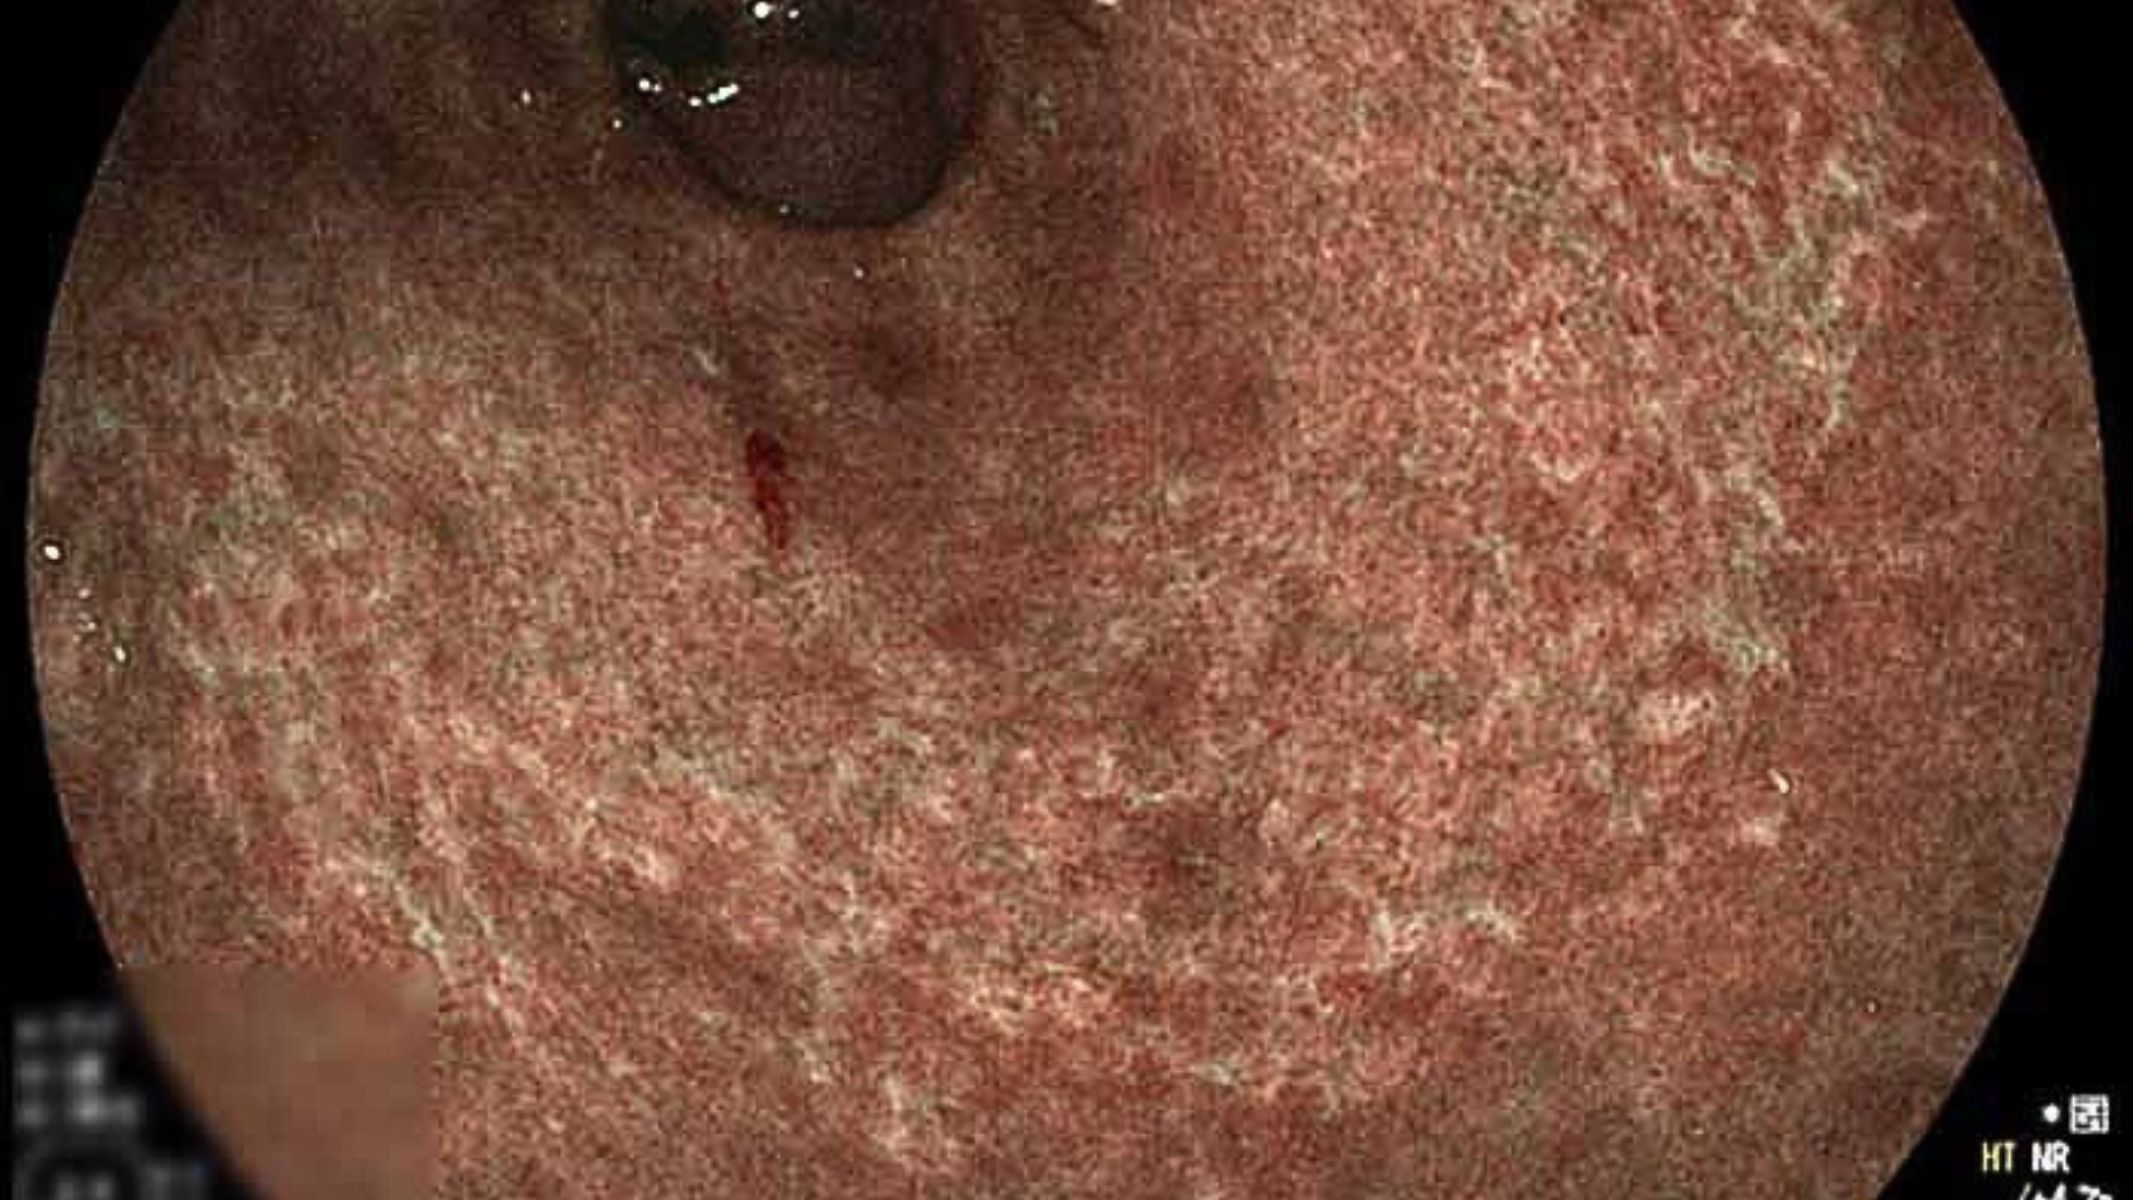

Hình ảnh nội soi ở bệnh nhân viêm teo dạ dày thường cho thấy niêm mạc dạ dày bị mỏng đi rõ rệt, các nếp niêm mạc trở nên phẳng, mất độ đàn hồi và giảm khả năng bài tiết chất nhầy bảo vệ. Niêm mạc có màu nhạt, đôi khi xuất hiện các vùng viêm rải rác hoặc dị sản ruột. Tình trạng này phản ánh sự giảm sút số lượng tế bào tuyến - yếu tố làm suy giảm khả năng tiết acid hydrochloric và enzyme tiêu hóa quan trọng.

- Nội soi dạ dày, tá tràng: Là phương pháp then chốt, cho phép quan sát trực tiếp niêm mạc dạ dày bị mỏng, nhạt màu, mất nếp gấp hoặc có vùng dị sản ruột. Sinh thiết niêm mạc được thực hiện để xác định mức độ teo, phát hiện dị sản hoặc loạn sản theo phân loại hệ thống (OLGA, OLGIM).